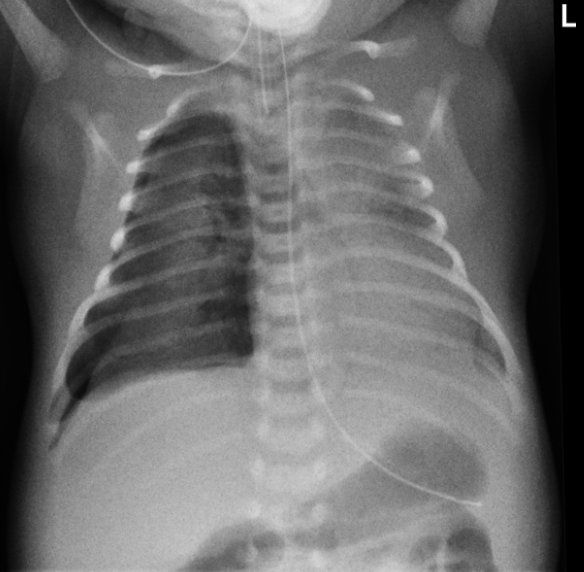

출생 시 체중이 1500g이었던 재태기간 30주의 미숙아가 호흡곤란증후군 치료를 받고 있었으나, 생후 5일째 갑작스럽게 호흡곤란과 청색증이 악화되었다. 이에 의료진이 촬영한 가슴 X선 사진 결과를 바탕으로 적절한 치료 방법을 결정해야 한다. 가장 적절한 치료 방법은 무엇인가?

신생아 호흡곤란증후군(Respiratory Distress Syndrome, RDS) 치료를 받던 중 '갑자기' 호흡곤란과 청색증이 발생하여 시행한 가슴 X선에서 기흉이 관찰된다. 현재 호흡곤란과 청색증 등 심한 증상을 보이고 있으므로 흉관삽입을 통해 감압을 해주어야 한다.

• 신생아 호흡곤란증후군으로 인한 페외 공기 누출(기흉, 종격동 기종, 폐사이질 기종)은 RDS가 있는 초극소 조산아 3~9%에서 발생할 수 있다. 출생 후 소생술 과정이나 출생 초기 기계 환기 적용 중 과도한 압력이나 과도한 일회 호흡량이 전달 되는 것이 원인이며, 자발 호흡에도 발생할 수 있다고 한다.